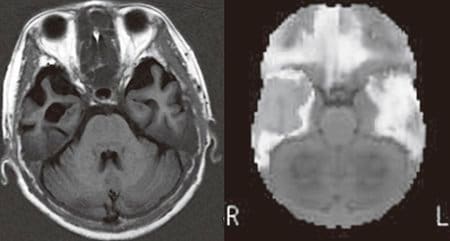

左:MRI像、右:脳血流SPECT像。60代女性。お金の計算もできて、買い物に行っても同じ物を買ってくることはない。夫の顔も覚えている。しかし「言葉が分からなくなった」と困っていた。頭部MRIでは両側(特に右側)の側頭葉に萎縮がみ られる。脳血流SPECT(3D-SSP)では明らかにその場所の血流が低下していた。アルツハイマー型認知症で特徴的とされる後部帯状回、楔前部の血流低下は認めない。この方は左利きなので、右側に言語機能があるようである

[図表2]前頭側頭型認知症の脳画像 左:MRI像、右:脳血流SPECT像。60代女性。お金の計算もできて、買い物に行っても同じ物を買ってくることはない。夫の顔も覚えている。しかし「言葉が分からなくなった」と困っていた。頭部MRIでは両側(特に右側)の側頭葉に萎縮がみ られる。脳血流SPECT(3D-SSP)では明らかにその場所の血流が低下していた。アルツハイマー型認知症で特徴的とされる後部帯状回、楔前部の血流低下は認めない。この方は左利きなので、右側に言語機能があるようである